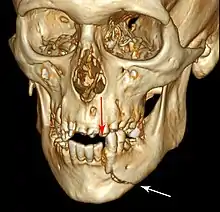

3D CT reconstruction of mandible fracture, white arrow marks fracture, red arrow marks moderate displacement and open bite